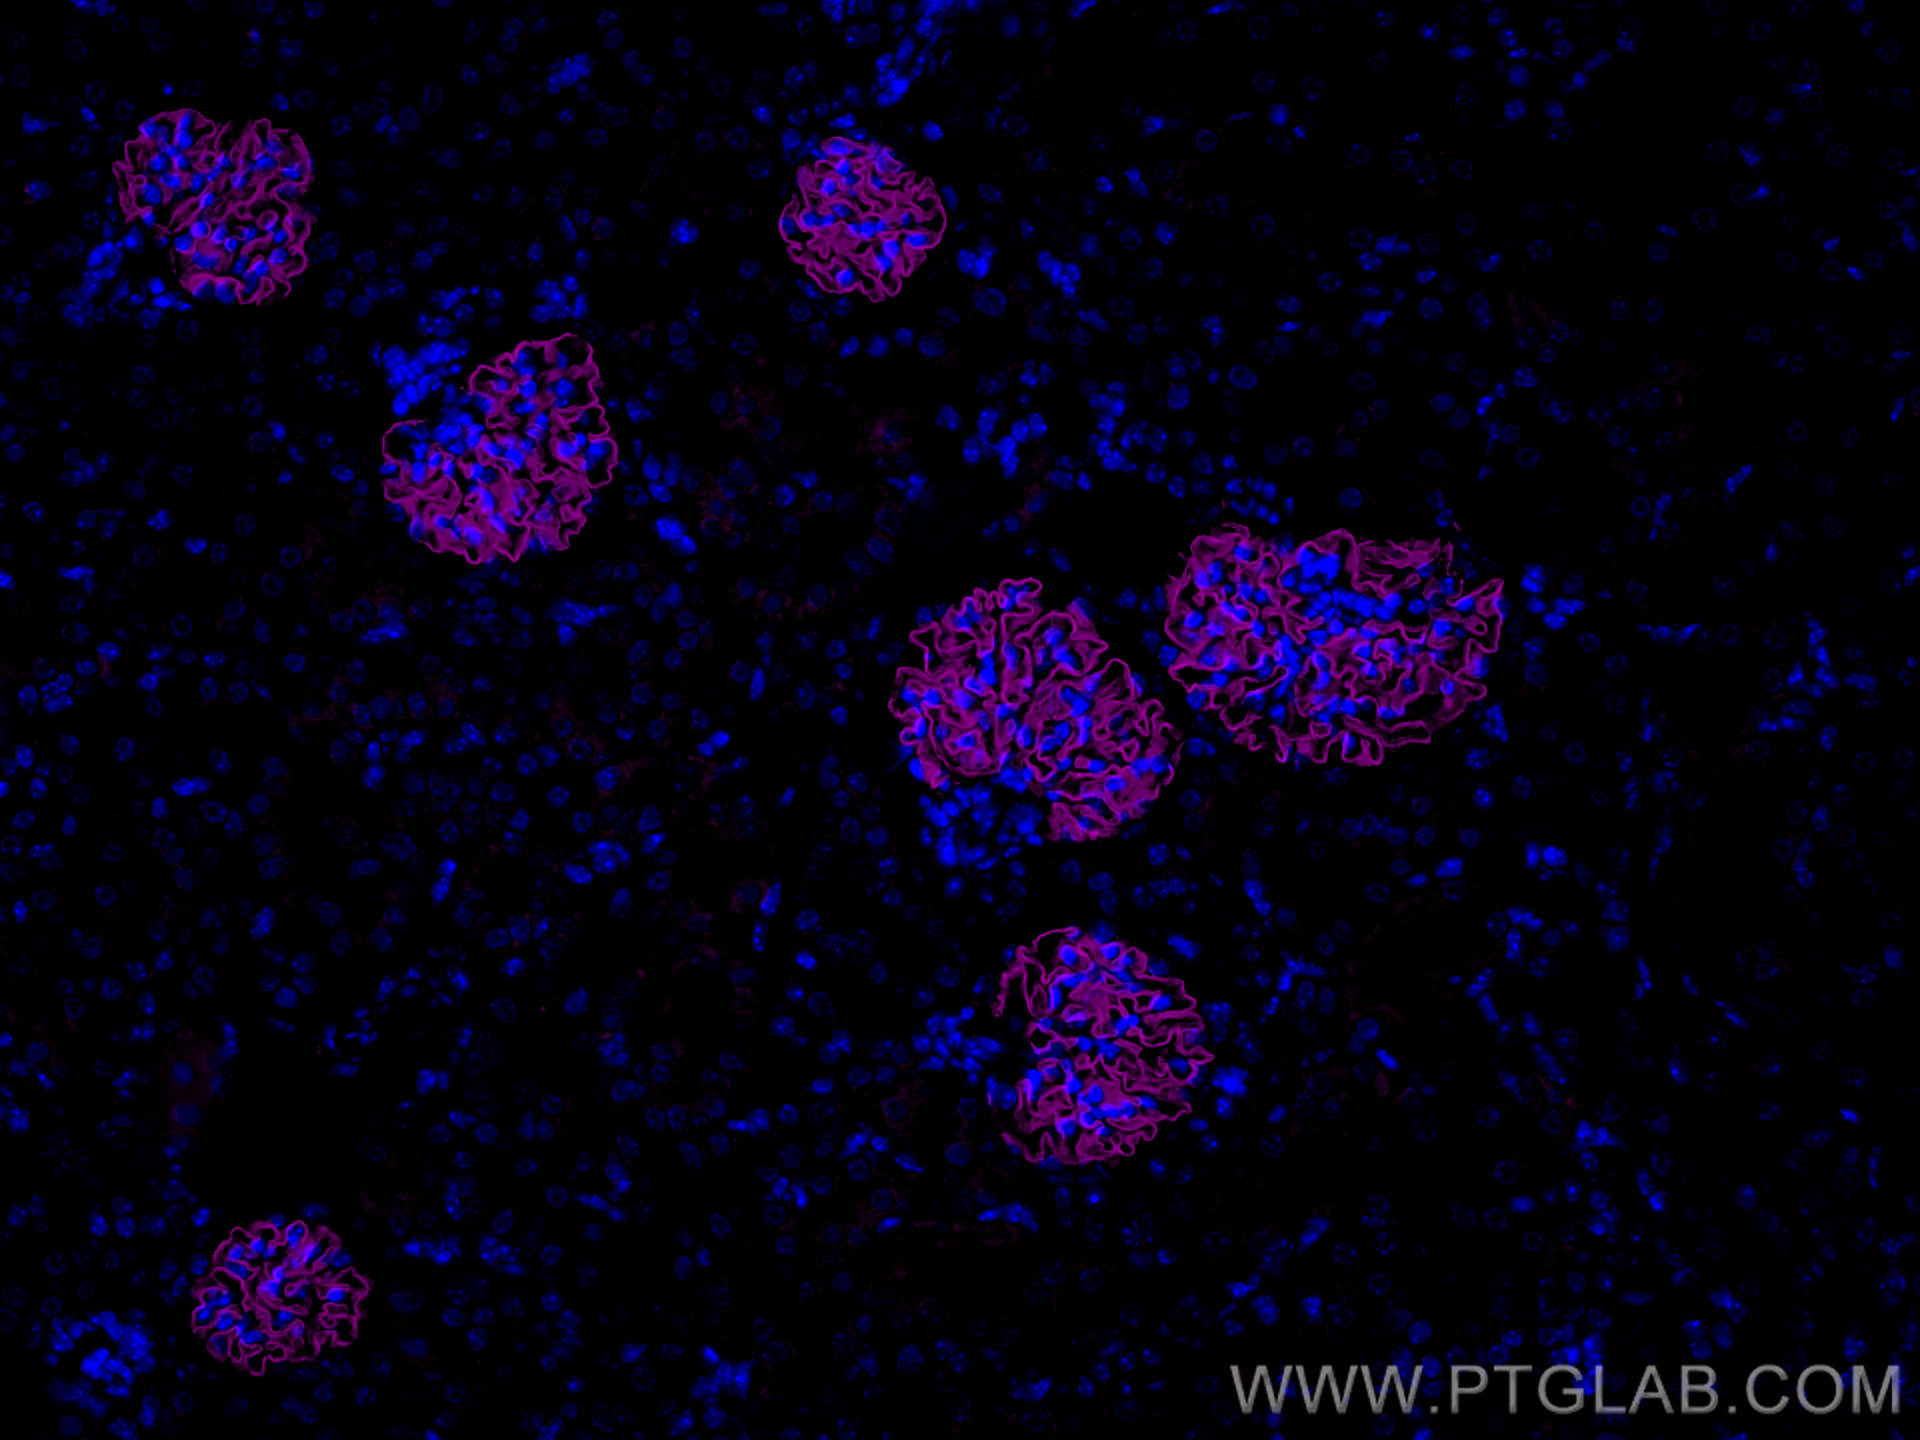

| Positive IF detected in | mouse kidney tissue, zebrafish embryos |